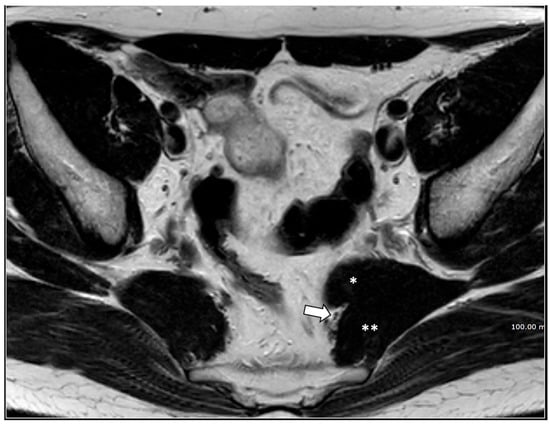

MRI in Chronic Pudendal Neuralgia: Diagnostic Criteria and Associated Pathologies

by Michele Gaeta, Sofia Turturici, Karol Galletta, Carmelo Geremia, Attilio Tuscano, Aurelio Gaeta, Marco Cavallaro, Salvatore Silipigni and Francesca Granata

Diagnostics 2026, 16(2), 326; https://doi.org/10.3390/diagnostics16020326 (registering DOI) - 20 Jan 2026

Background/Objectives: Chronic pudendal neuralgia is a relatively rare condition in the general population, with an incidence of 1%. Although diagnosis of pudendal neuralgia is mainly clinical, Magnetic Resonance Imaging (MRI) is commonly performed to obtain further information. However, clear criteria and guidelines for [...] Read more.

Background/Objectives: Chronic pudendal neuralgia is a relatively rare condition in the general population, with an incidence of 1%. Although diagnosis of pudendal neuralgia is mainly clinical, Magnetic Resonance Imaging (MRI) is commonly performed to obtain further information. However, clear criteria and guidelines for MRI diagnosis and the clinical–radiological correlation are still not definite. Methods: We reviewed 81 patients with chronic pudendal neuralgia, studied by an MRI designed protocol for a pelvis and pelvic floor examination. A key element of the protocol was the use of a diffusion-weighted imaging (DWI) technique with echo planar imaging (EPI) sequence (b-values of 0, 100, and 600) for the neurographic evaluation of the nerve. Results: MRI examination revealed DWI abnormalities in 42/81 patients. Pudendal nerve abnormalities were unilateral in 33/42 patients and bilateral in 9/42. Moreover, in 23/42 patients, pathologies related to a high probability of neuropathy have been identified. Conclusions: This study highlights the role of pelvic MRI as a valuable imaging modality in the evaluation of patients with chronic pudendal neuralgia. In the study protocol we propose, an essential role is played by the DWI technique, which improves the visual definition of the pudendal nerve and related anatomical structures. By focusing on anatomical visualization and structured image interpretation, our work provides a practical imaging-oriented contribution to a field in which standardized MRI evaluation is still lacking. Full article